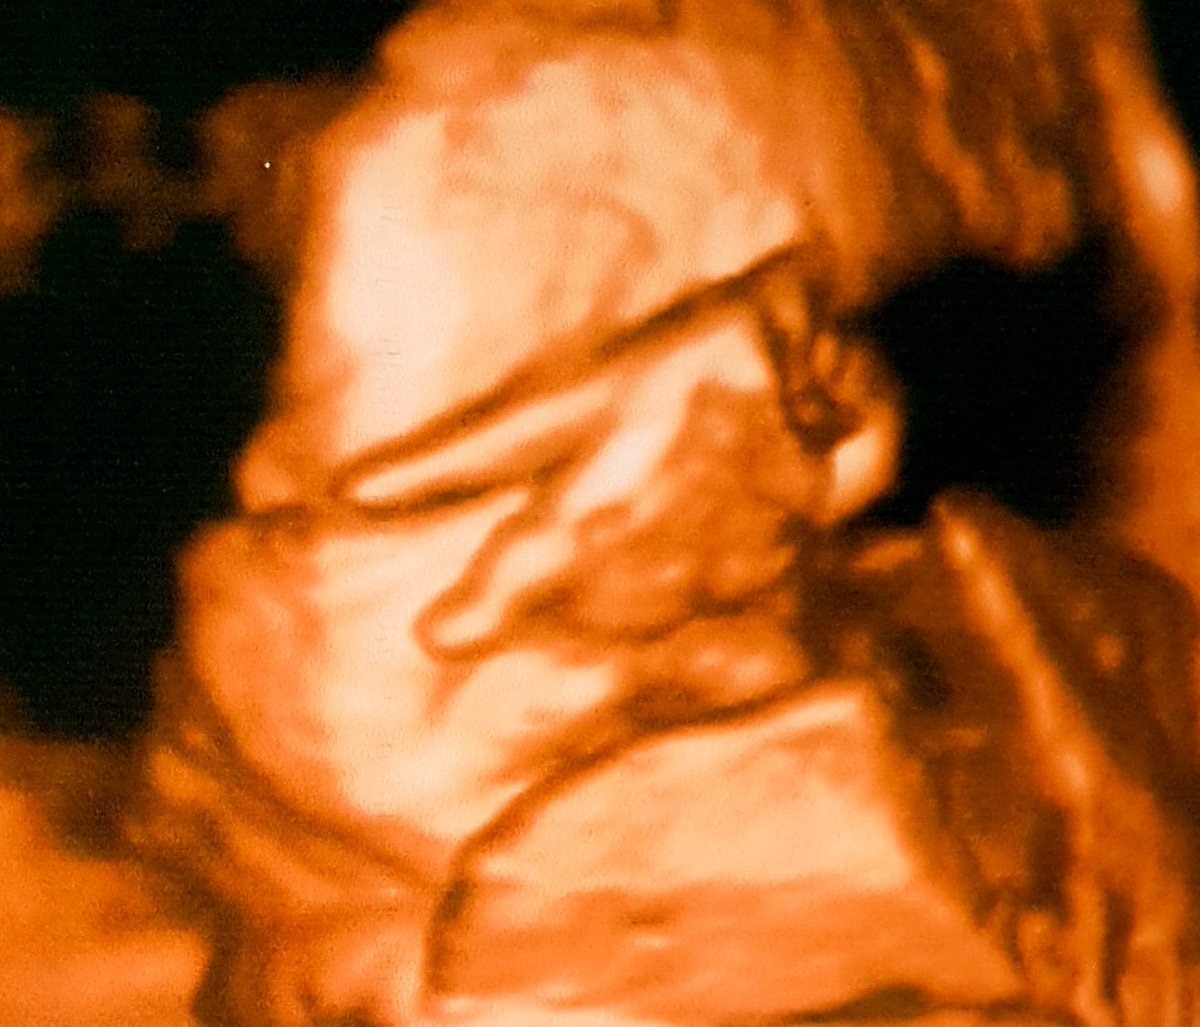

As much as you want to plan your life it has a way of surprising you with unexpected things that will make you amazed. 36weeks today, we're good✌🏻

36weeks today, we're good✌🏻